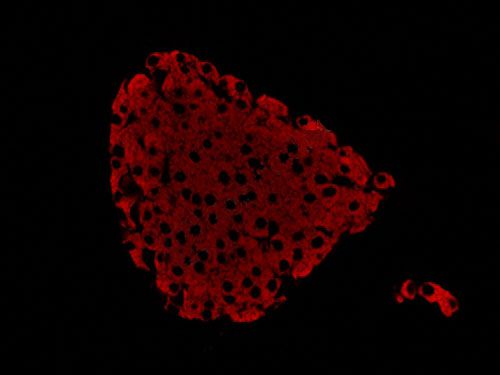

熒光顯微鏡是免疫熒光的基本工具。它是由光源、濾板系統和光學系統等主要部件組成。是利用一定波長的光激發標本發射熒光,通過物鏡和目鏡系統放大以觀察標本的熒光圖像。

正置顯微鏡型號:NIKON Eclipse ci;軟件:NIS_F_Ver43000_64bit_E;成像系統:NIKON digital sight DS-FI2。可選擇100×、200×和400×不同放大倍數。共配置紅、綠、藍三個通道:DAPI(EX激發340-380,BA發射435-485);FITC(EX激發465-495,BA發射515-555);G-2A(EX激發510-560,BA發射590)

實驗結果展示:

(3)實驗結果:圖片×6,每張圖片包括merge圖,單通道圖(常規選擇同視野下200×3、400×3)